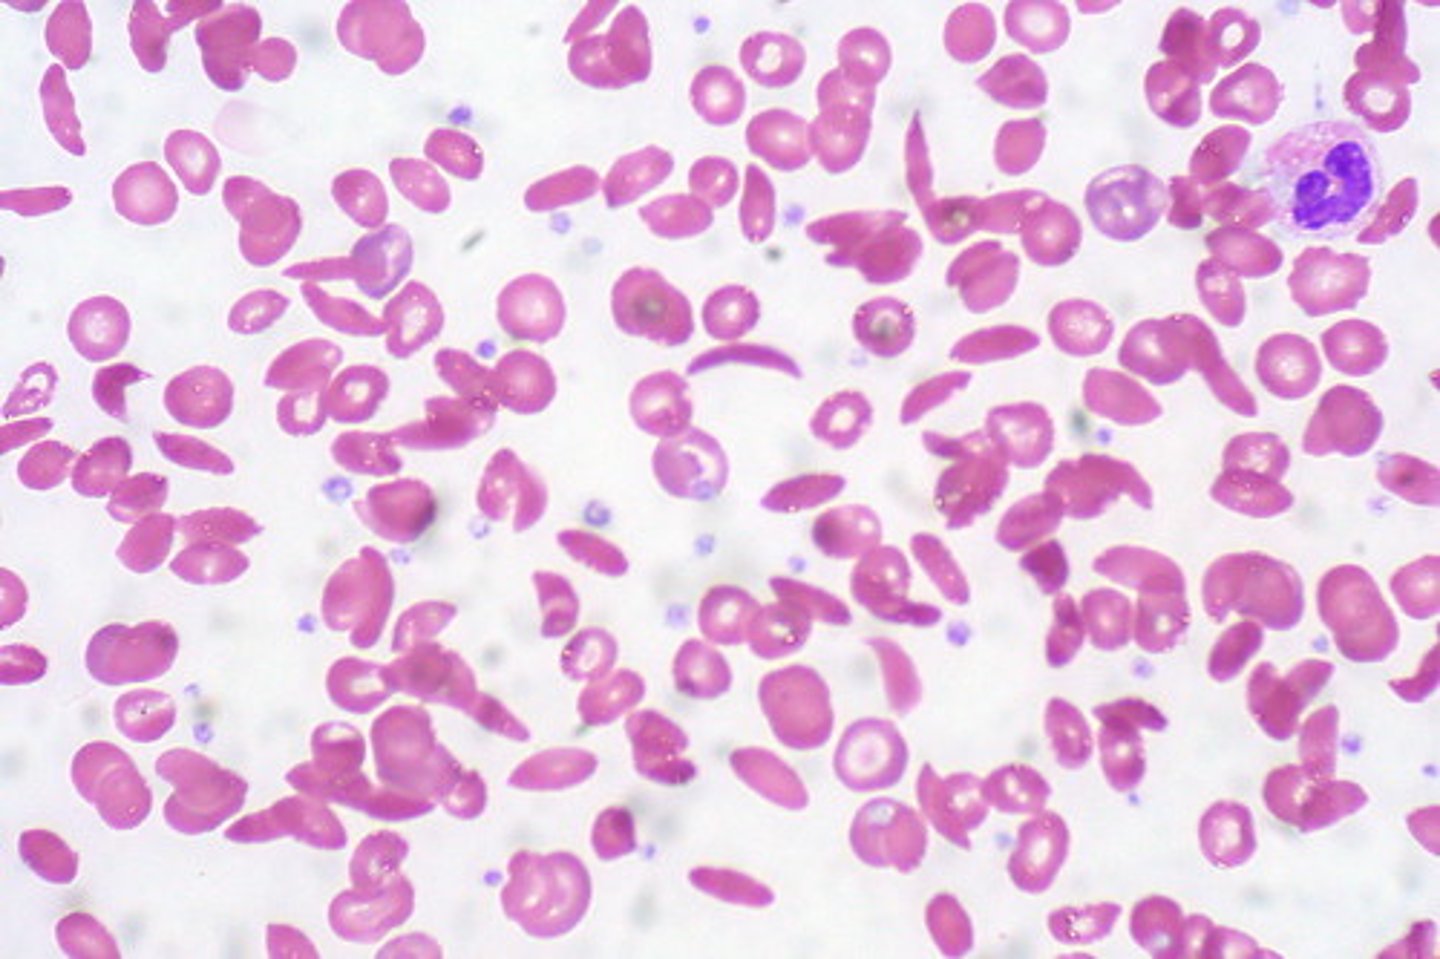

Blood

What is this?

Abnormal

Is this blood slide normal or abnormal?

Neutrophil

what is this?

lymphocyte

what is this?

Macrophage

what is this?

Eosinophil

what is this?

monocyte

what is this?

basophil

what is this?

platelet

what is this?

Red Blood Cell

what is this?